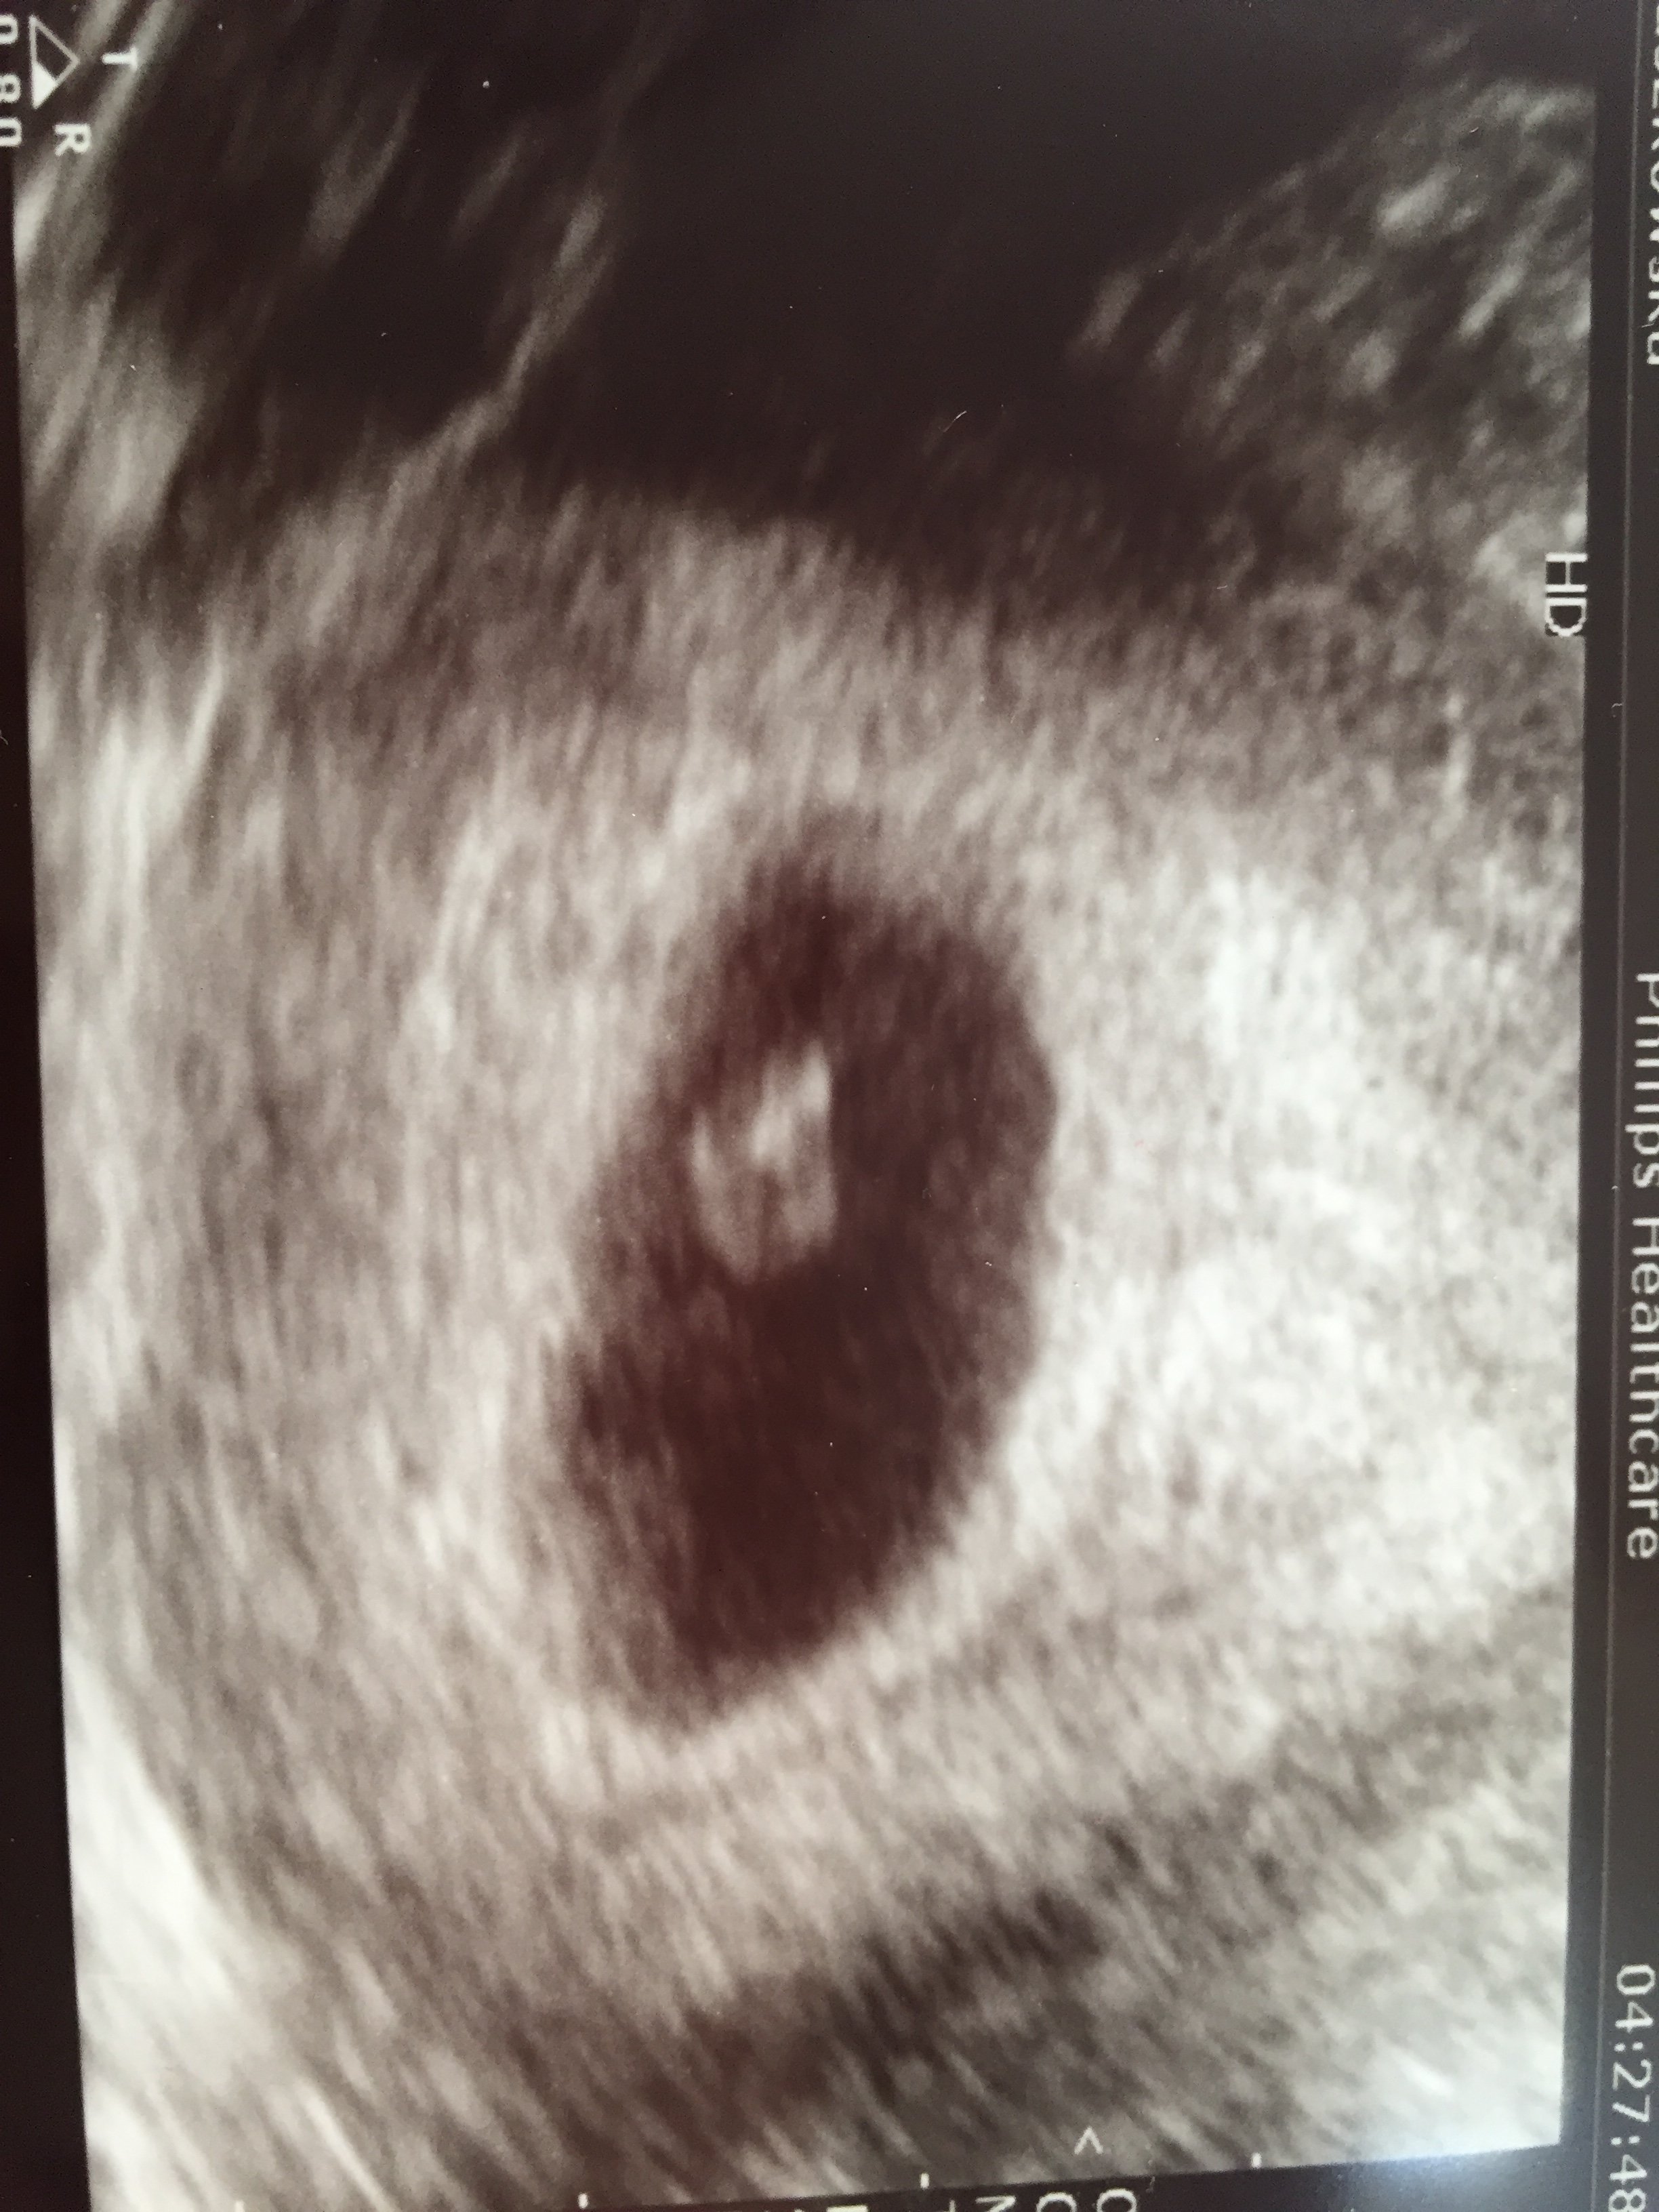

To mój człowieczek :-)

A wiec tak:

Na wizycie dostalam recepte na dupka lepiej dmuchac na zimne.

Lekarz odrazu mi powiedzial ze dzis badania nie bedzie bo ciaza za mloda i nic nie bedzie widac a nie chce mnie stresowac za tydzien bede miec USG.

Jutro mam powtorzyc bete i jak bede miec wynik ok 130 w gore to mam sie nie martwic.

Wiec mam stresa do przyszlego tygodnia